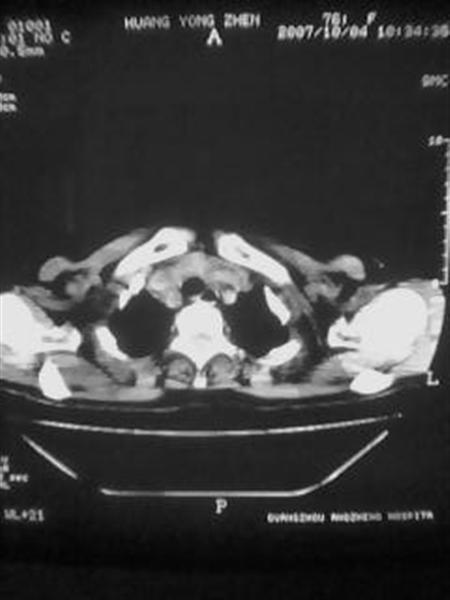

标题: CT10080:F76Y,各位老师发表高见!!! [打印本页]

标题: CT10080:F76Y,各位老师发表高见!!!

右下肺周围型肺癌伴双肺右侧叶间 胸膜及右肺门淋巴结转移